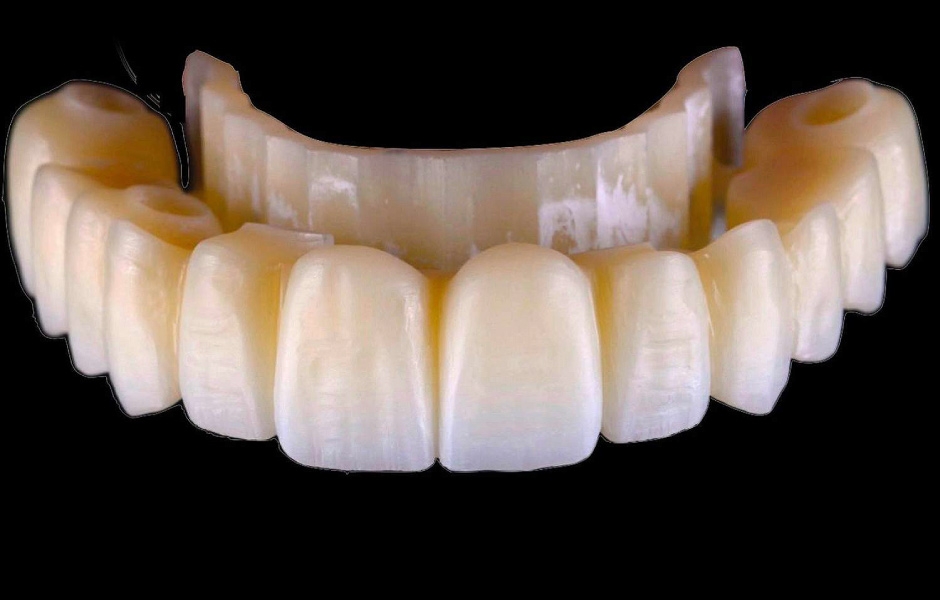

Použití plně navigovaného chirurgického protokolu ve spojení s kompletně digitálním postupem zhotovení protetiky umožnilo přesný návrh a následné vyfrézování provizorních náhrad z PMMA (obr. 34–35).

Obr. 34

Obr. 35